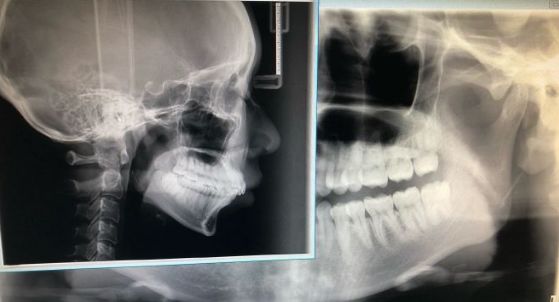

为了能拍出最能还原病情的照片,需要单反相机,微距镜头,环形闪光灯等外,还需要开口器、反光镜以及背景板等专业辅助器材用品。

所以,随手一拍的照片,恐怕是瞧不出什么,更何况牙医看病不仅仅是望诊,还有探诊,扪诊等。